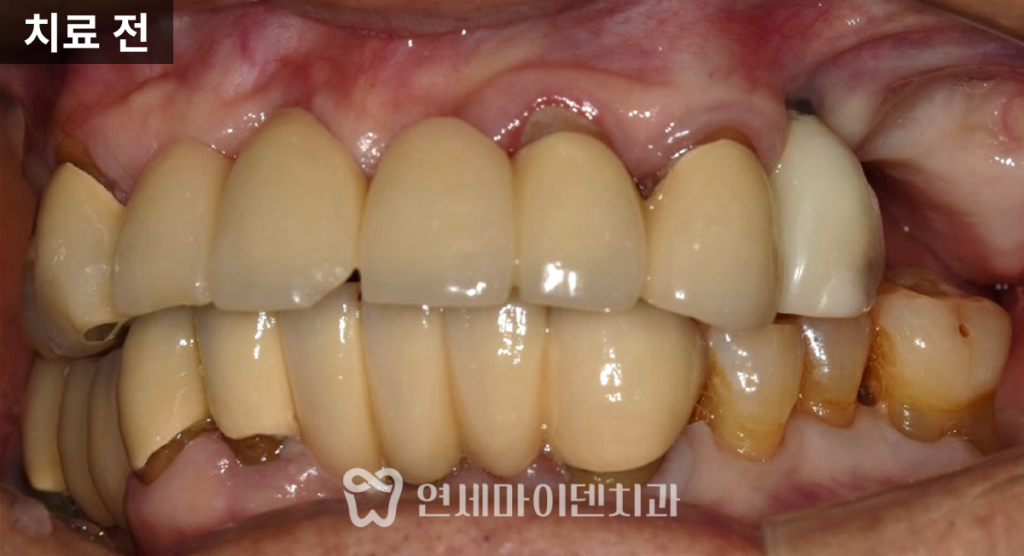

어머님은 이미 한쪽은 치아가 거의 없어 식사가 어려웠고,

반대쪽으로만 겨우 식사를 하고 계셨습니다.

문제는 그 유일하게 사용하던 쪽에서

임플란트 주변으로 염증과 고름이 반복되면서,

더 이상 식사가 쉽지 않다는 점이었습니다.